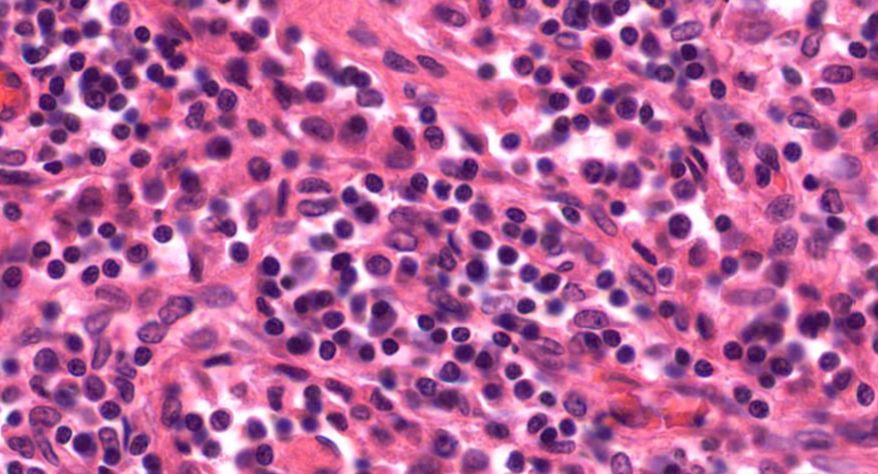

低倍镜:胸腺表面包有薄层结缔组织构成的被膜,结缔组织深入实质,将胸腺分成许多不完整的小叶。每个小叶分为周围的皮质和中央的髓质两部分。皮质中胸腺细胞排列密集,故染色深;髓质中胸腺细胞较少,胸腺上皮细胞多,故染色浅,其中可见染成红色的圆形小体-胸腺小体。高倍镜:胸腺小体大小不等,由几层至十几层扁平的胸腺上皮细胞呈同心圆状排列而成,其外周的细胞较幼稚,细胞核明显;小体中央部分的上皮细胞已退化,细胞核消失,胞质呈均质状,染成红色。